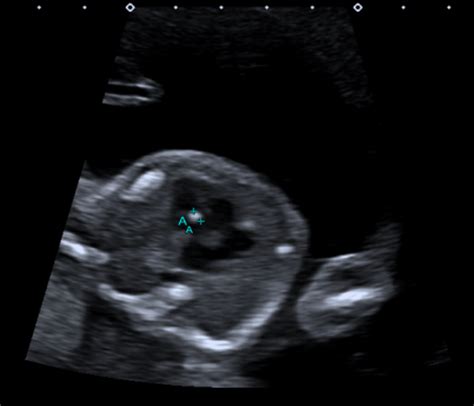

So, why is this scan so important? Well, the main goal is to check your baby’s development and look for any potential abnormalities. During the scan, a trained sonographer will carefully examine the baby’s organs, including the brain, heart, spine, kidneys, and limbs. They also assess the placenta, the amount of amniotic fluid, and the umbilical cord. This comprehensive check-up helps to identify any structural issues or potential problems early on, which allows for further investigation, treatment, or planning after the baby is born. The 20-week scan is a standard part of prenatal care in South Africa and is a great way to gain peace of mind and prepare for the arrival of your little one. The sonographer will be looking at the baby’s overall growth, making sure everything is developing as it should. They will also be checking the baby’s position, which is often a fun part, as you might get a sneak peek at the baby’s gender if you wish to know! This scan is a crucial step in ensuring both the health of the baby and the mother.

So, what exactly happens during the 20-week scan in South Africa? It’s generally a non-invasive procedure, meaning it doesn’t involve any needles or instruments inserted into your body. You’ll typically lie down on a comfortable examination table, and the sonographer will apply a gel to your abdomen. This gel helps the ultrasound machine’s probe glide smoothly and ensures clear images. The sonographer will then move the probe over your belly, taking detailed measurements and images of your baby. The process usually takes about 30 to 45 minutes, but it can vary depending on the baby’s position and how clear the images are. The sonographer will be very focused, so it’s important to make sure you’re comfortable. You might even be able to see your baby’s face, hands, and feet on the screen. It’s a truly amazing experience to see your baby developing and growing. Sometimes, the sonographer might ask you to change positions or take a short walk to help the baby move into a better position for imaging. Make sure you drink enough water beforehand, as a full bladder can sometimes improve the image quality. Don’t hesitate to ask questions during the scan. The sonographer is there to help you understand what they are seeing and to address any concerns you may have.